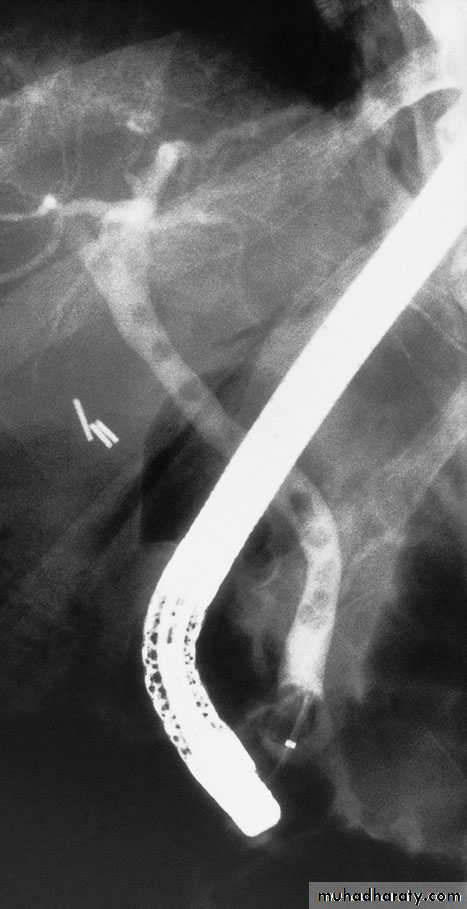

68Endoscopic retrograde cholangiopancreatography: thepatient presented with jaundice 4 days after laparoscopic cholecystectomy.The bile duct contained multiple stones